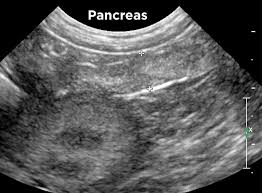

A vet answers 10 commonly asked questions about cancer in dogs. Altogether, the most common pancreatic cancer in dogs and cats are insulinomas, followed by adenocarcinomas. We do see, commonly, dogs under 18 months of age with terminal cancer. Addressing pancreatic cancer in dogs is thankfully fairly rare but, when it is encountered, it is, unfortunately, a very serious condition. Pancreatic adenocarcinomas are the most common malignant tumor of the exocrine pancreas in dogs.

Risks Associated With Canine Acute Pancreatitis from www.pethealthnetwork.com Pancreatic cancer in dogs several types of cancer have been reported in the pancreas. Pancreatic cancer, although admittedly rare in canines, can be quite aggressive and fairly destructive for dogs. The reason why a particular pet may develop this, or any tumor or cancer, is not straightforward. Pancreatic adenocarcinoma in dogs a neoplasm, or tumor, can be either benign or malignant in nature. A study was made with five dogs. Fortunately, exocrine pancreatic cancer in dogs is uncommon. There are a number of. 169 cancer patients and healthy volunteers were mixed into a group.

Pancreatitis In Dogs Symptoms Treatment Prevention from cdn.akc.org Unfortunately, this is not the most common cause of pancreatitis. Pancreatic cancer often goes undetected until it's advanced and difficult to treat. Bicarbonate neutralizes the highly acidic stomach contents as they move into the intestines. A vet answers 10 commonly asked questions about cancer in dogs. Pancreatic cancer pancreatic cancer is often hard to detect until the condition is at advanced stages, which is why the prognosis for dogs with this type of cancer is usually dire. The most common form of malignant pancreatic cancer in dogs is called pancreatic adenocarcinomas. Weight loss, loss of appetite, fever, abdominal pain, vomiting, diarrhea, and lethargy. A study was made with five dogs.

In reality, 90% of the time, the inciting cause of pancreatitis in dogs is idiopathic (cannot be determined). The presence of these tumors cause the dog's insulin levels to increase, in turn decreasing the glucose in their bloodstream. Fortunately, exocrine pancreatic cancer in dogs is uncommon. As a result, pancreatic conditions such as pancreatitis, pancreatic cancer, canine diabetes and stomach cancer in dogs have all been on the rise. Thankfully, pancreatic cancer is relatively rare in dogs, but the most common types are adenocarcinomas and insulinomas. As in many other forms of cancers, canine pancreatic cancer occurs more commonly in older dogs. Tips to help your dog eat. Pancreatic cancer pancreatic cancer is often hard to detect until the condition is at advanced stages, which is why the prognosis for dogs with this type of cancer is usually dire. Without a functioning pancreas, dogs can become weak and suffer neurological problems. These tumours can be either benign or malignant. What used to be a disease of the old is now unfortunately a disease of the young. in this video series, the cause most often cited for the supposed epidemic is commercial pet food, though vaccines, parasite preventatives, environmental toxins, and many other purported. Pancreatic cancer usually strikes older dogs aged 9 to 10, although younger mature dogs can contract it too, and some breeds appear more susceptible than others, says the veterinary society of surgical oncology. When pancreatic cancer occurs in dogs, the first signs usually resemble those of pancreatitis:

Pancreatic Cancer In Dogs Innovet Pet from cdn.shopify.com Two portuguese water dogs and three labradors. A few other types of cancer have also been reported in the pancreas. Some of the other risk factors for pancreatic cancer include smoking, chronic pancreatitis (inflammation of the pancreas), family history of pancreatic cancer, obesity and certain genetic syndromes. Thankfully, pancreatic cancer is relatively rare in dogs, but the most common types are adenocarcinomas and insulinomas. Both of these tumors are more common in dogs than cats. At every phase of life, but when illness is involved, the role of nutrition. The reason why a particular pet may develop this, or any tumor or cancer, is not straightforward. Pancreatic cancer, although admittedly rare in canines, can be quite aggressive and fairly destructive for dogs.